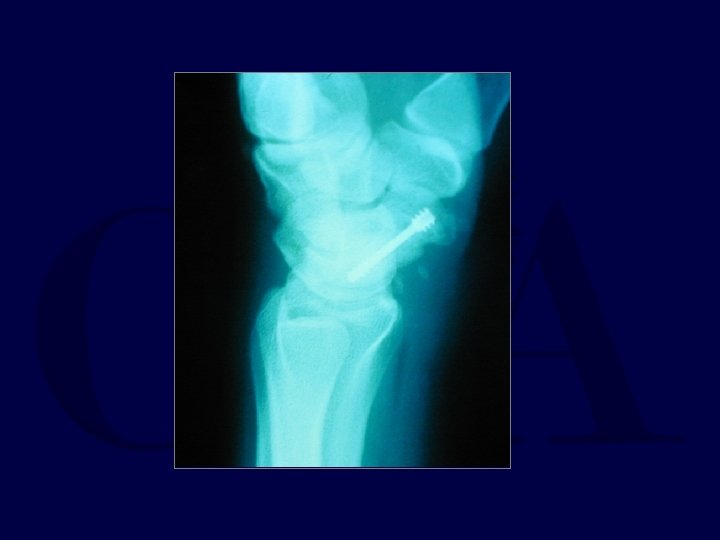

Trans-scaphoid Perilunate Dislocations

Fix scaphoid first: dorsal approach

Pin L-T and Mid-carpal joints

Make sure Radius -Lunate-Capitate are colinear and S -L angle restored